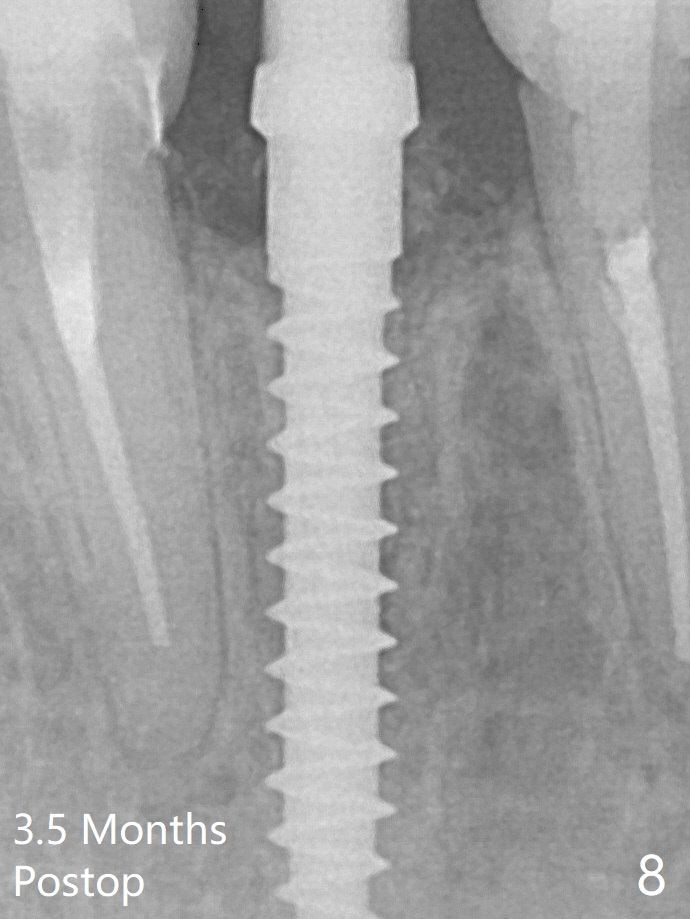

A drawback of implant planning at #25 is not to use a preop PA (Fig.1 (^ fracture line)). The initial trajectory seems to be alright (Fig.2 (red line: socket; D: 1.2 mm drill)), but a 2.5x14(2) mm implant placed is close to the tooth #26 (Fig.3 (allograft having been placed)). The latter may be related to more bone loss in the distal crest 3.5 months postop (Fig.8) and more severe distal papillary recession (Fig.9 *). The meisal bone seems to be wider.